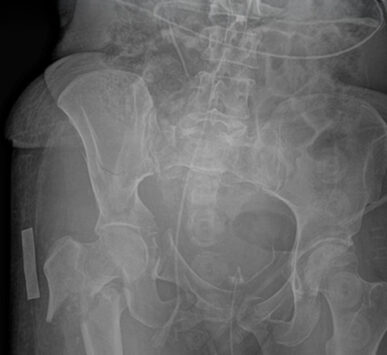

Entre sus áreas de especialización, se encuentran el tratamiento de fracturas complejas, la cirugía de pelvis y acetábulo mínimamente invasiva y la reconstrucción ósea con fijadores circulares para el tratamiento de pseudoartrosis e infecciones.

La osteoporosis es una enfermedad en la que los huesos se vuelven frágiles y porosos.